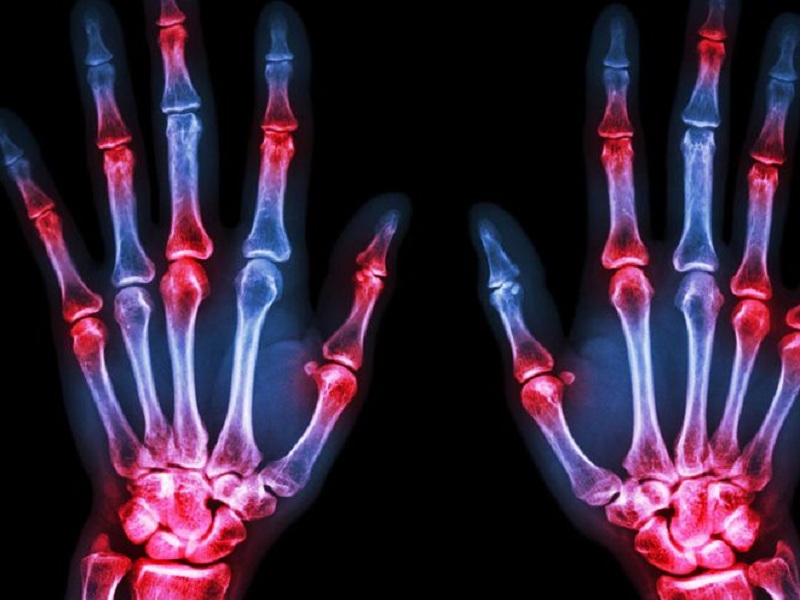

Gli individui con un maggiore apporto di fibre di cereali hanno minori probabilità di andare incontro a sviluppo di artrite reumatoide secondo uno studio

Gli individui con un maggiore apporto di fibre di cereali hanno minori probabilità di andare incontro a sviluppo di artrite reumatoide (AR). Queste le conclusioni principali di uno studio pubblicato su Nature Scientific Reports, che ha anche osservato come il punteggio dell’Indice Infiammatorio Dietetico sia un “intermediario cruciale” in questa relazione, evidenziando il ruolo della dieta nella prevenzione e nella gestione dell’AR.